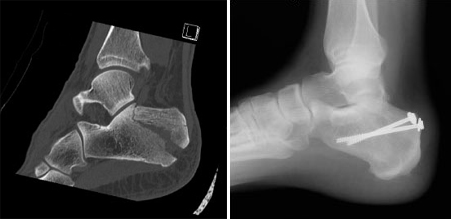

• Percutaneous screw fixation. If the bone pieces are large, they can sometimes be moved back into place without making a large incision. Special screws are then inserted through small incisions to hold the fracture together.

Screw fixation of calcaneus fracture

(Left) A displaced fracture of the calcaneus. (Right) The fracture has been reduced and the bones held in place with screws.

• Open reduction and internal fixation. During this operation, an open incision is made to reposition (reduce) the bones into their normal alignment. They are held together with wires or metal plates and screws.

Internal fixation of calcaneus (heel bone) fracture

In this X-ray, the bone fragments have been realigned and held in place with metal plates and screws.